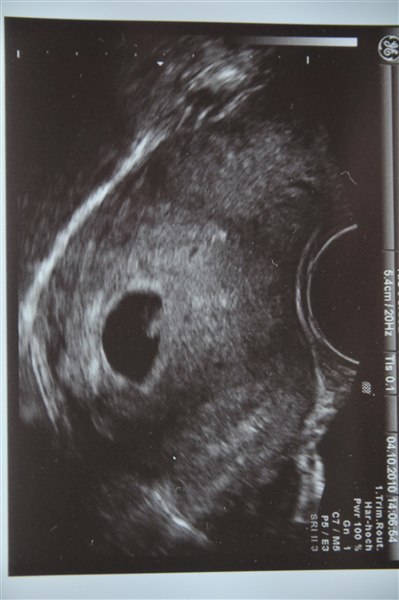

Var jeg til i mandags. Jeg havde egentlig ikke de store forventninger om at se noget særligt, da jeg ved denne undersøgelse med Malte blev slemt bekymret, da han var en hel del mindre end foirventet på det tidspunkt og der var ingen hjerteblink at se. Men alt så fint ud, der var en lille klump på 4,2 mm og fine hjerteblink

Det er jo ikke meget, man kan se på dette tidspunkt, men det var nu alligevel hyggeligt at se hjerteblinkene

Nå, men jeg tog lige et billede af scanningsbilledet, hvis nogen har lyst til at se?